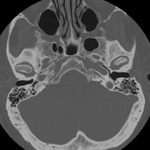

Cranial base

Axial